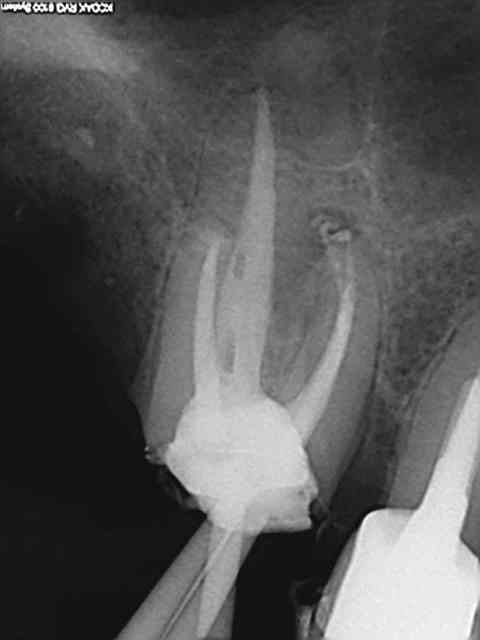

Et puis si une autre pour la route.)))))